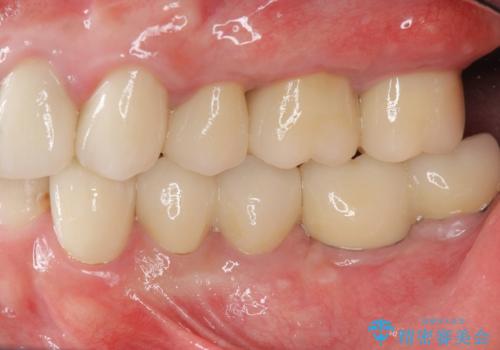

矯正治療を絡めた総合的な治療をお行なったことで、理想的な咬合関係を確立し安定した噛み合わせで仕上げることができました。

また歯周外科を行うことで歯ぐきの腫れを改善し、清掃性を高めています。